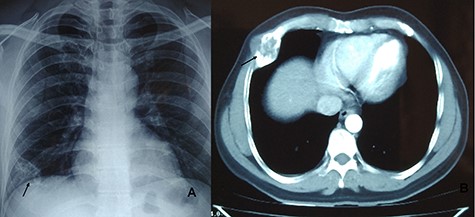

A 15-year-old girl present with lump in right chest with gradually progressing discomfort of 6-month duration. The discomfort was constant with intermittent exacerbation. She had no history of trauma or prior chest surgery, and her past medical history was unremarkable. Her physical examination revealed a palpable mildly tender mass on sixth rib on anterolateral wall of the right chest. Her routine laboratory test results, including complete blood count, erythrocyte sedimentation rate, renal function test and liver function tests, were all within normal range. Chest radiograph performed showed destruction of right sixth rib (Fig. 1A). CT chest revealed 36 × 30 × 80 mm well-defined large uniloculated cystic lesion of the sixth rib involving anterolateral part and abutting the costochondral junction (Figs 1B and C). She underwent surgery after all diagnostic investigation was completed.

CXR (A, arrow) showing mass lesion in sixth rib. CT chest axial (B, arrow) and saggital (C) showing uniloculated bone cyst.